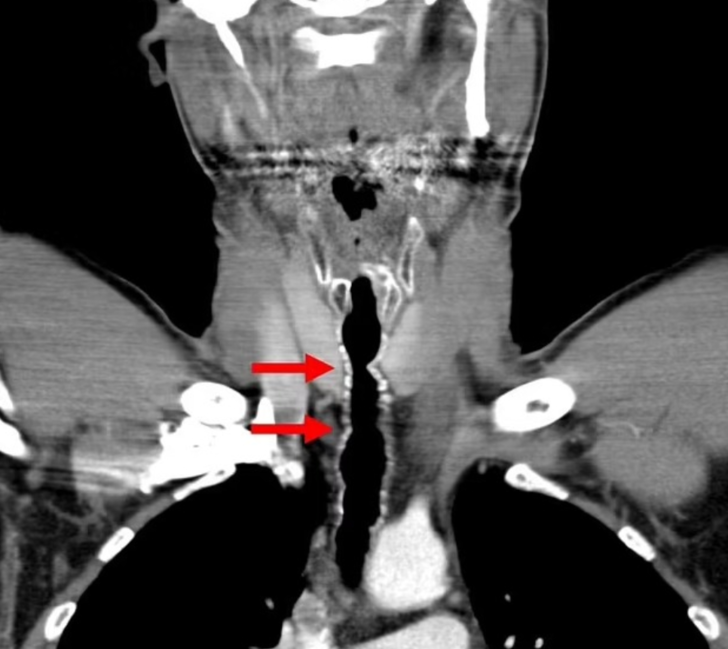

Sağlık görevlileri solunum yollarına küçük bir kamera göndererek inceleme yapmaya karar verdiler ve burada boğazında birkaç koyu renkli kıl çıktığını keşfettiler. Başlangıçta doktorlar tüyleri almayı başardılar ve bu da adama geçici bir rahatlama sağladı.

Talihsiz adama endotrakeal kıllanma veya boğazda kıllanma adı verilen son derece nadir bir durum teşhisi konuldu. Kesin olarak söyleyemeseler de doktorlar saç büyümesinin muhtemelen sigara içme alışkanlığından kaynaklandığına inanıyorlar.